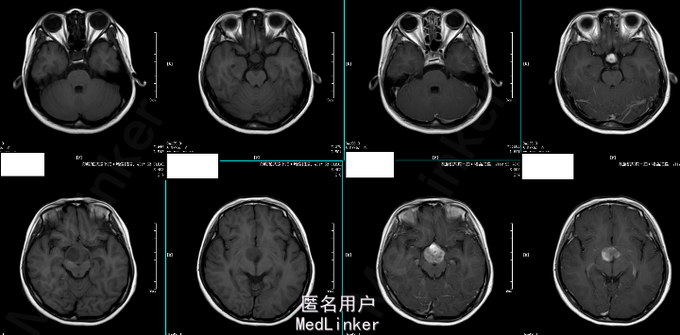

女 11岁 学生 主诉:2014年5月无明显诱因出现头晕,偶有头痛,双眼视力下降,步态正常。外院头颅MRI提示“鞍上占位性病变,累及蝶鞍,多为生殖细胞瘤,不完全除外颅外咽鼓管瘤”。 既往史、个人史、家族史未见异常。

T 36.1℃ P 80bpm,R 20bpm,BP 100/65mmHg。心肺腹未见明显异常。神经查体未见命像一场。 辅助检查:2014-06-20外院头颅MRI:鞍上占位性病变,累及蝶鞍,多为生殖细胞瘤,不完全除外颅外咽鼓管瘤 2014-07-08我院头颅MR增强:鞍区占位性病变,考虑生殖细胞来源的肿瘤可能性大。 b-HCG 13.53ng/ml,AFP 224.84ng/ml。

诊断:鞍上区恶性肿瘤:颅内生殖细胞肿瘤 处理:放疗。(3D-CRT 36GY/FX),胸腺肽增强免疫力及副作用对症处理。 (2015-06-24复查头颅MR结果如下)